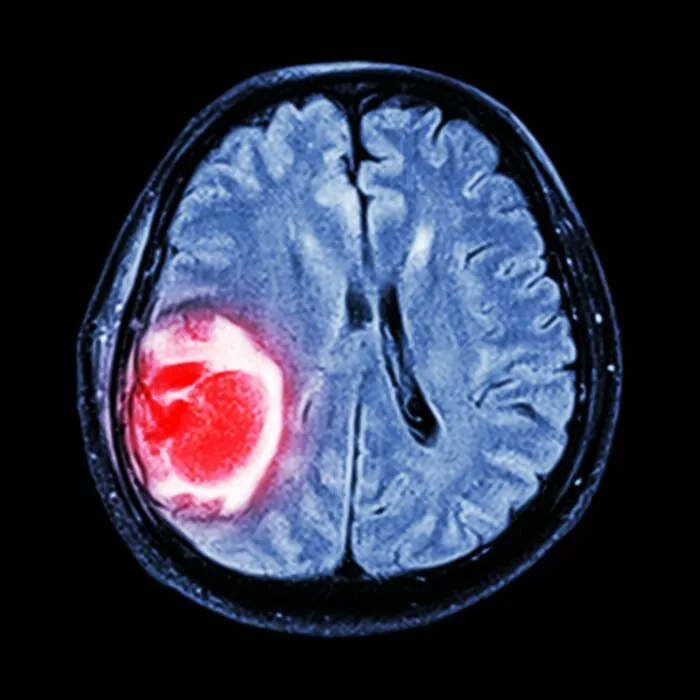

Bei Moore wurde ein Glioblastom diagnostiziert, eine aggressive Form von Krebs, die das Gehirn oder das Rückenmark befallen kann. Obwohl sich Moore im Juli dieses Jahres einer Operation sowie einer Strahlen- und Chemotherapie unterzog, um das Fortschreiten des Krebses zu verlangsamen, stellten die Ärzte fest, dass die Krankheit tödlich war und ihr Leben auf tragische Weise verkürzt werden würde.